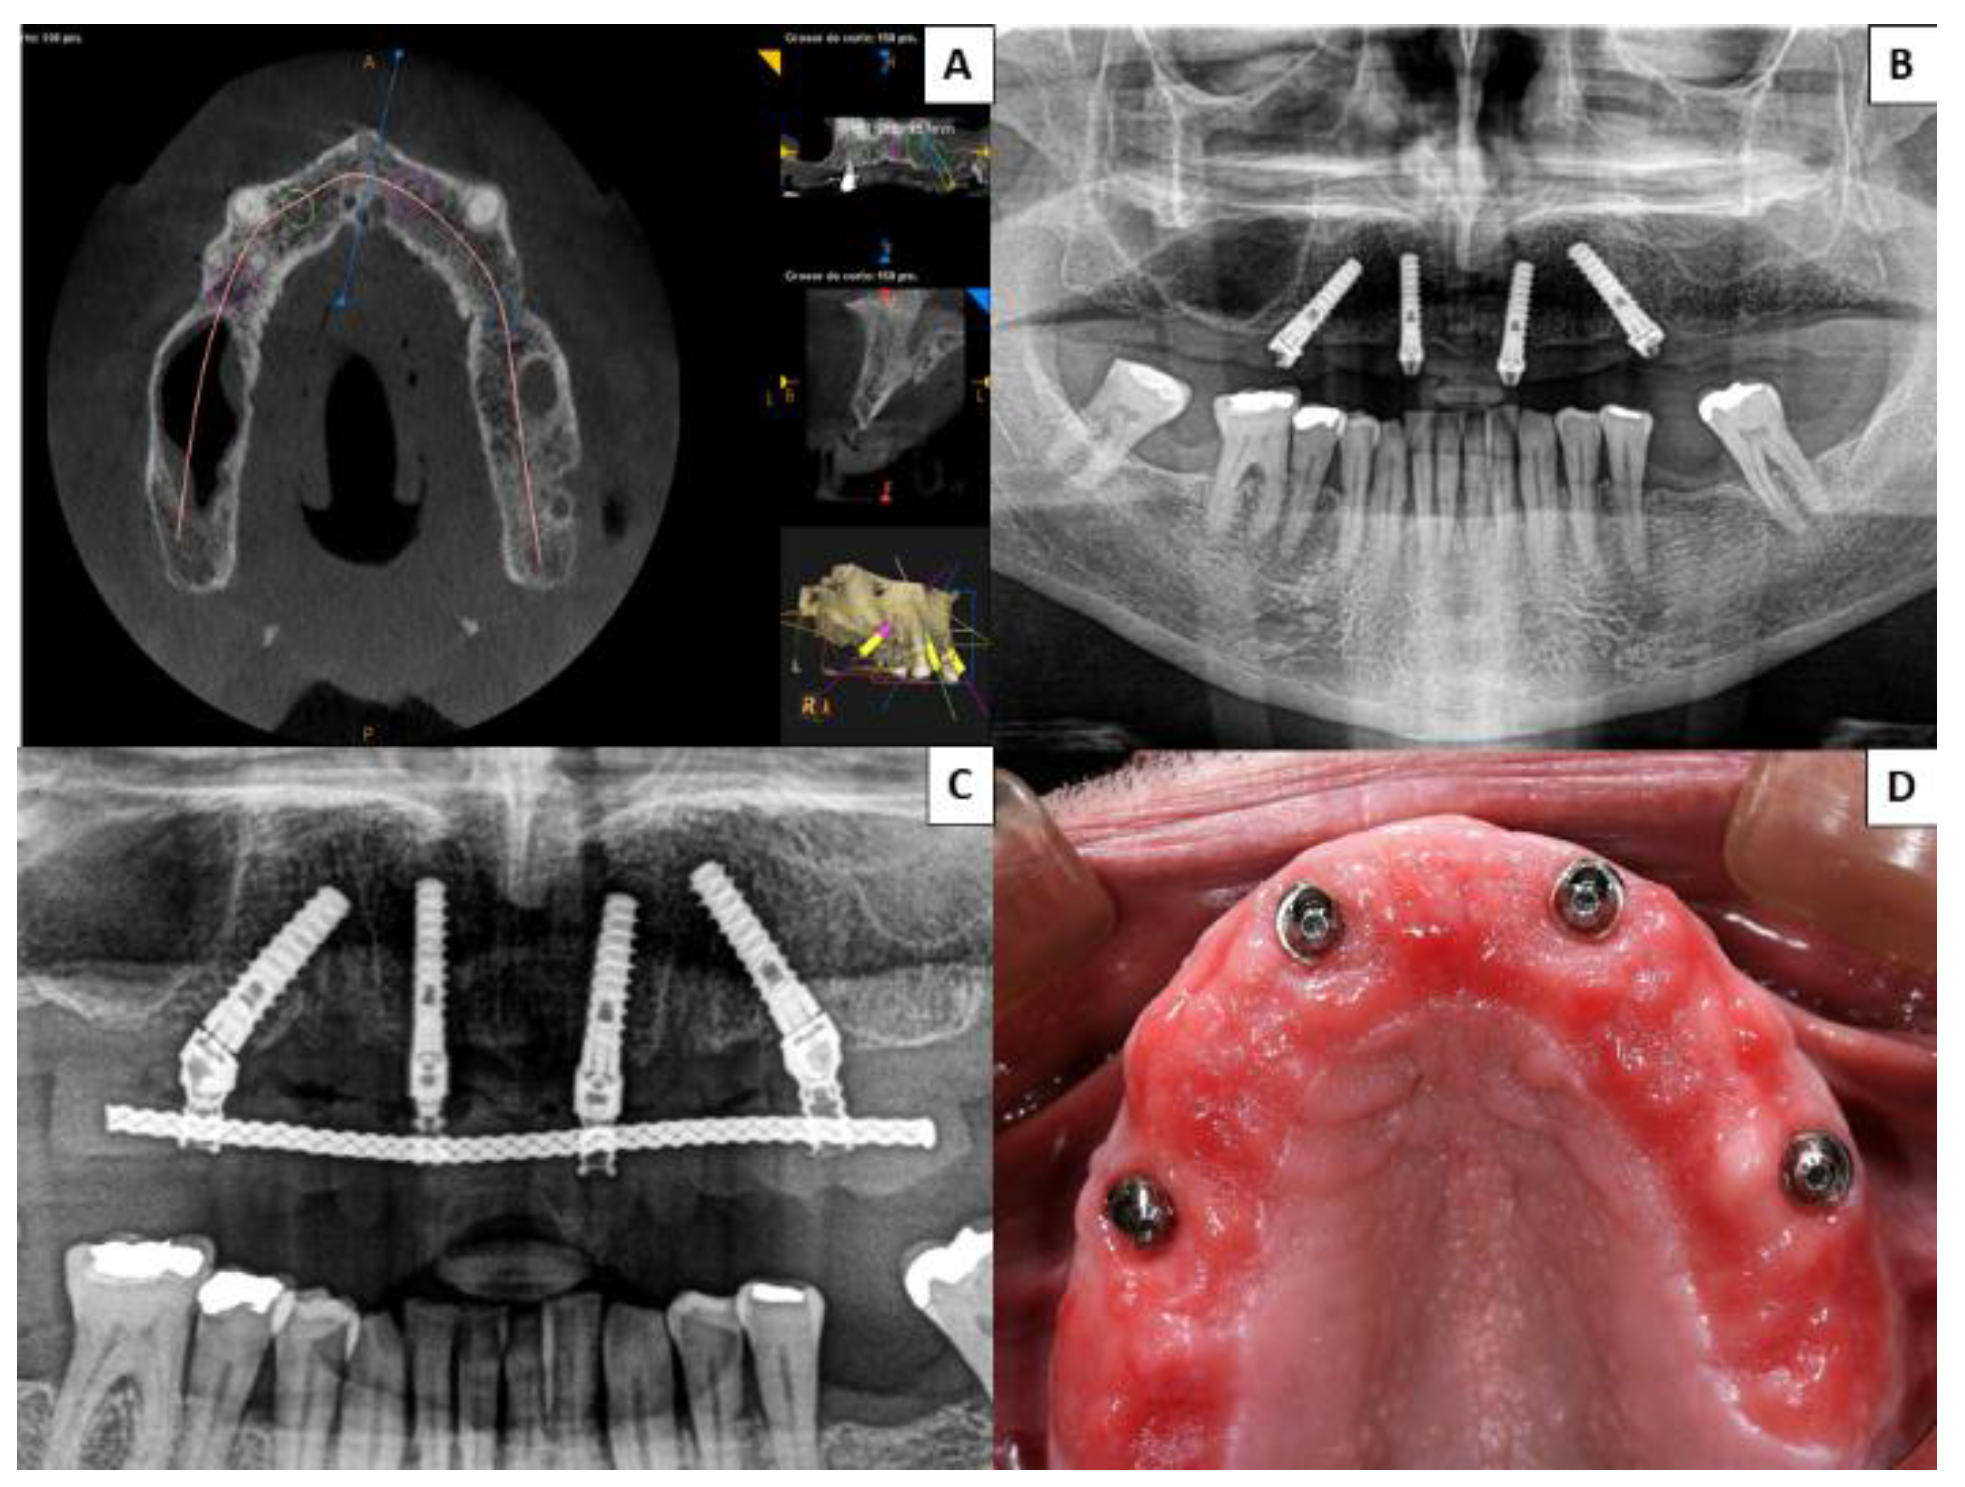

Figure 3. Group 2 patient rehabilitated with four conventional implants in the premaxilla following the all-on-four concept; two placed axially and the other two angled between 35° and 45°. (A) Presurgical planning with cone-beam computed tomography (CBCT) of implant distribution. (B,C) Postsurgical orthopantomographs taken 6 months after surgery to ensure correct fit of definitive prosthesis. (D) At a follow-up check-up, a patient complained of food debris trapped beneath the fixed prosthesis; when the prosthesis was unscrewed the patient was found to present mucositis.